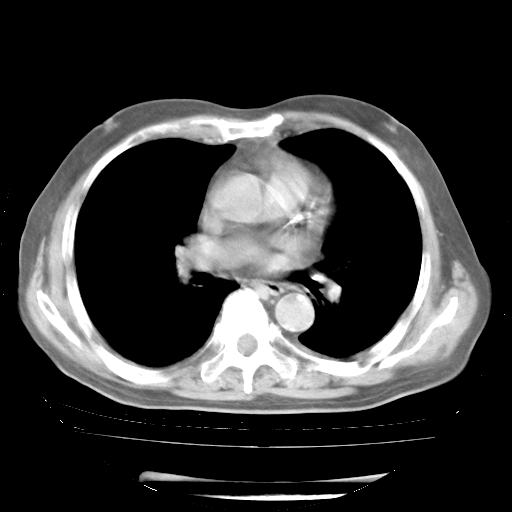

4月28日肺部CT——再次出现类似去年5月9日——透光度降低,“间质性”改变。

4月28日肺部CT——再次出现类似去年5月9日——磨玻璃样、间有“粟粒样”改变。

4月28日肺部CT

个人阅读4.14日肺部CT平扫:纵隔窗无异常,但肺窗示:双下肺内、后基底段有片絮状侵润影,部位以后基底段为著,以间质改变为主,呈急性肺泡炎征像,和首次住院影像学有相似之处。仅是个人读片,明日请相关专家再读片哈。其它建议同上。

1、108#的是4月14日的胸部CT(发此贴时还没看着28日的CT)。14日的胸部CT其实已经出现改变(如108#所述),个人认为28日的胸部CT除纵膈窗疑似有双侧胸膜增厚或少量胸积液(可行胸部B超明确)外,与4月14日对照病变有所加重;2、已经给予“异烟肼、利福平、乙胺丁醇”抗痨治疗?如果是,甲强龙80mg可缓慢减量;如果环磷酰胺已停用,暂不使用;3、中性粒细胞92%,明显升高,目前体温情况?注意合并细菌感染可能,使用左氧氟沙星情况下,是否联用B-内酰胺类抗菌药物?另外是查免疫全套非风湿全套。

今请临免主任会诊后认为:4月14日胸部CT已有双下肺间质性改变。患者病情复发多系激素减量过快不正规所致。目前甲强龙80mg/日,一周后酌情开始减量,不易过快。环磷酰胺若已停用,暂不使用。他同意目前抗菌药物使用,但应考虑是否加用B-内酰胺类抗菌药物(中性细胞明显增高);2、结核复发目前依据不足;3、若免疫全套各项指标正常,考虑多系特发性肺间质炎可能大。4、加强支持,并注意保护胃黏膜。